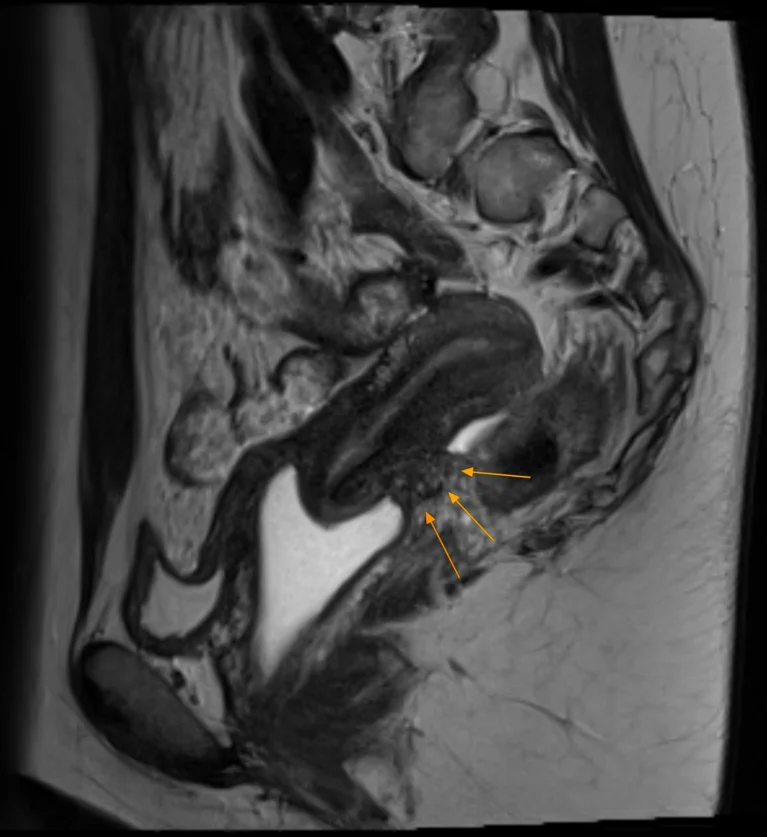

Tiefliegende Endometrioseknoten im Torus uterinus mit blutenden Stellen | |||